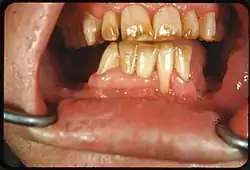

- Tobacco: Tar in smoke from tobacco products (and also smokeless tobacco products) tends to form a yellow-brown-black stain around the necks of the teeth above the gumline.[12]